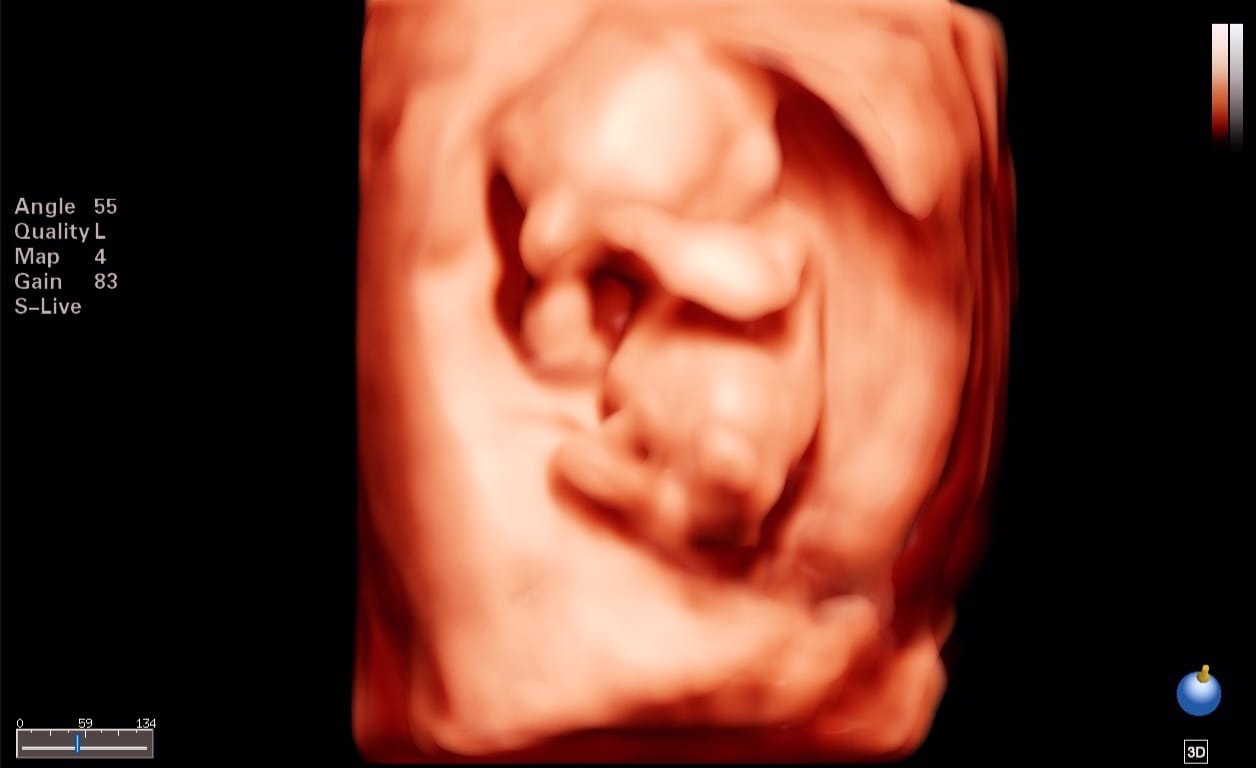

- Te proporcionamos tecnología en alta resolución, con la cual podrás ver una imagen a color en tiempo real de tu bebé ,proporciona una visión temprana y más transparente de la anatomía fetal, va más allá de la superficie para revelar hasta sus huesitos, órganos y otras estructuras internas, aportando una mayor capacidad de diagnóstico.

Esta ecografía se realiza desde las 11 semanas hasta las 13 semanas + 6 días. La exploración generalmente se realiza por vía transabdominal, pero en algunos casos puede ser necesario realizar el examen por vía Transvaginal. Esta es una de las exploraciones más importantes durante el embarazo y nos ayuda:

La exploración se realiza entre las 18 y 24 semanas de gestación. Ideal 20 a 22 Semanas de gestación. Durante la exploración, examinamos cada parte del cuerpo fetal, determinamos la posición de la placenta, evaluamos la cantidad de líquido amniótico y medimos el crecimiento fetal. Se presta especial atención al cerebro, la cara, la columna vertebral, el corazón, el estómago, los intestinos, los riñones y las extremidades. Dentro de los objetivos Principales de la Ecografia Morfologica son: